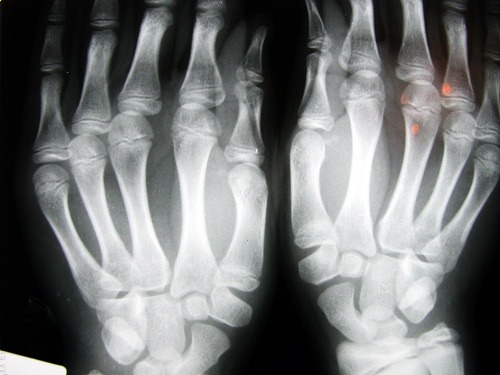

Um dos estudos mais conhecidos a respeito foi feito pelo doutor Donald Unges, que por mais de 60 anos manteve o hábito de estalar os dedos da mão esquerda duas vezes por dia, sem repetir a ação na mão direita.

Anualmente ele examinou suas mãos e nunca encontrou rastros de doenças degenerativas (inclusive na mão que estalava).

Outra pesquisa entrevistou trinta idosos em um asilo em Los Angeles. Aqueles que haviam estalado os dedos durante toda a vida não apresentaram osteoartrite.

Em um terceiro estudo, desta vez com adultos na faixa dos 45 anos, em Detroit, foi descoberto que o problema estava focado na força para segurar as coisas.

Ou seja, aqueles que costumavam estalar os dedos tinham menos força; e em mais de 80% dos casos, sofriam de inchaços nas mãos.